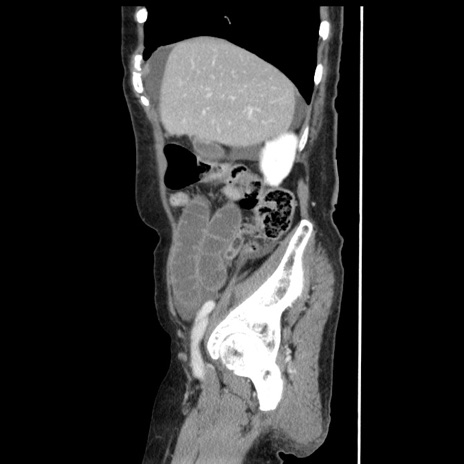

症例1(矢状断像)

【症例】80歳代女性

【主訴】腹痛

【現病歴】8時間前から腹痛あり来院。

【既往歴】糖尿病、脂質異常症、子宮体癌にて子宮全摘術

【身体所見】意識清明・会話良好だが腹痛で苦悶様、全腹部にわたって反跳痛と圧痛あり

【データ】WBC 13600、CRP 0.14、LDH 224、CK 90